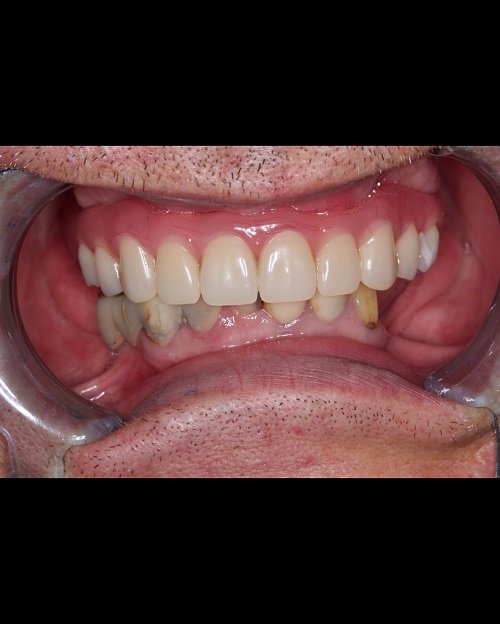

«Все на 4-х имплантатах»

«Все на 4-х имплантатах» - данную методику мы применяем нашим пациентам с полным отсутствием зубов.

Именно эта методика позволяет позволяет в кратчайшие сроки, около 3-5 дней зажить полноценной жизнью.